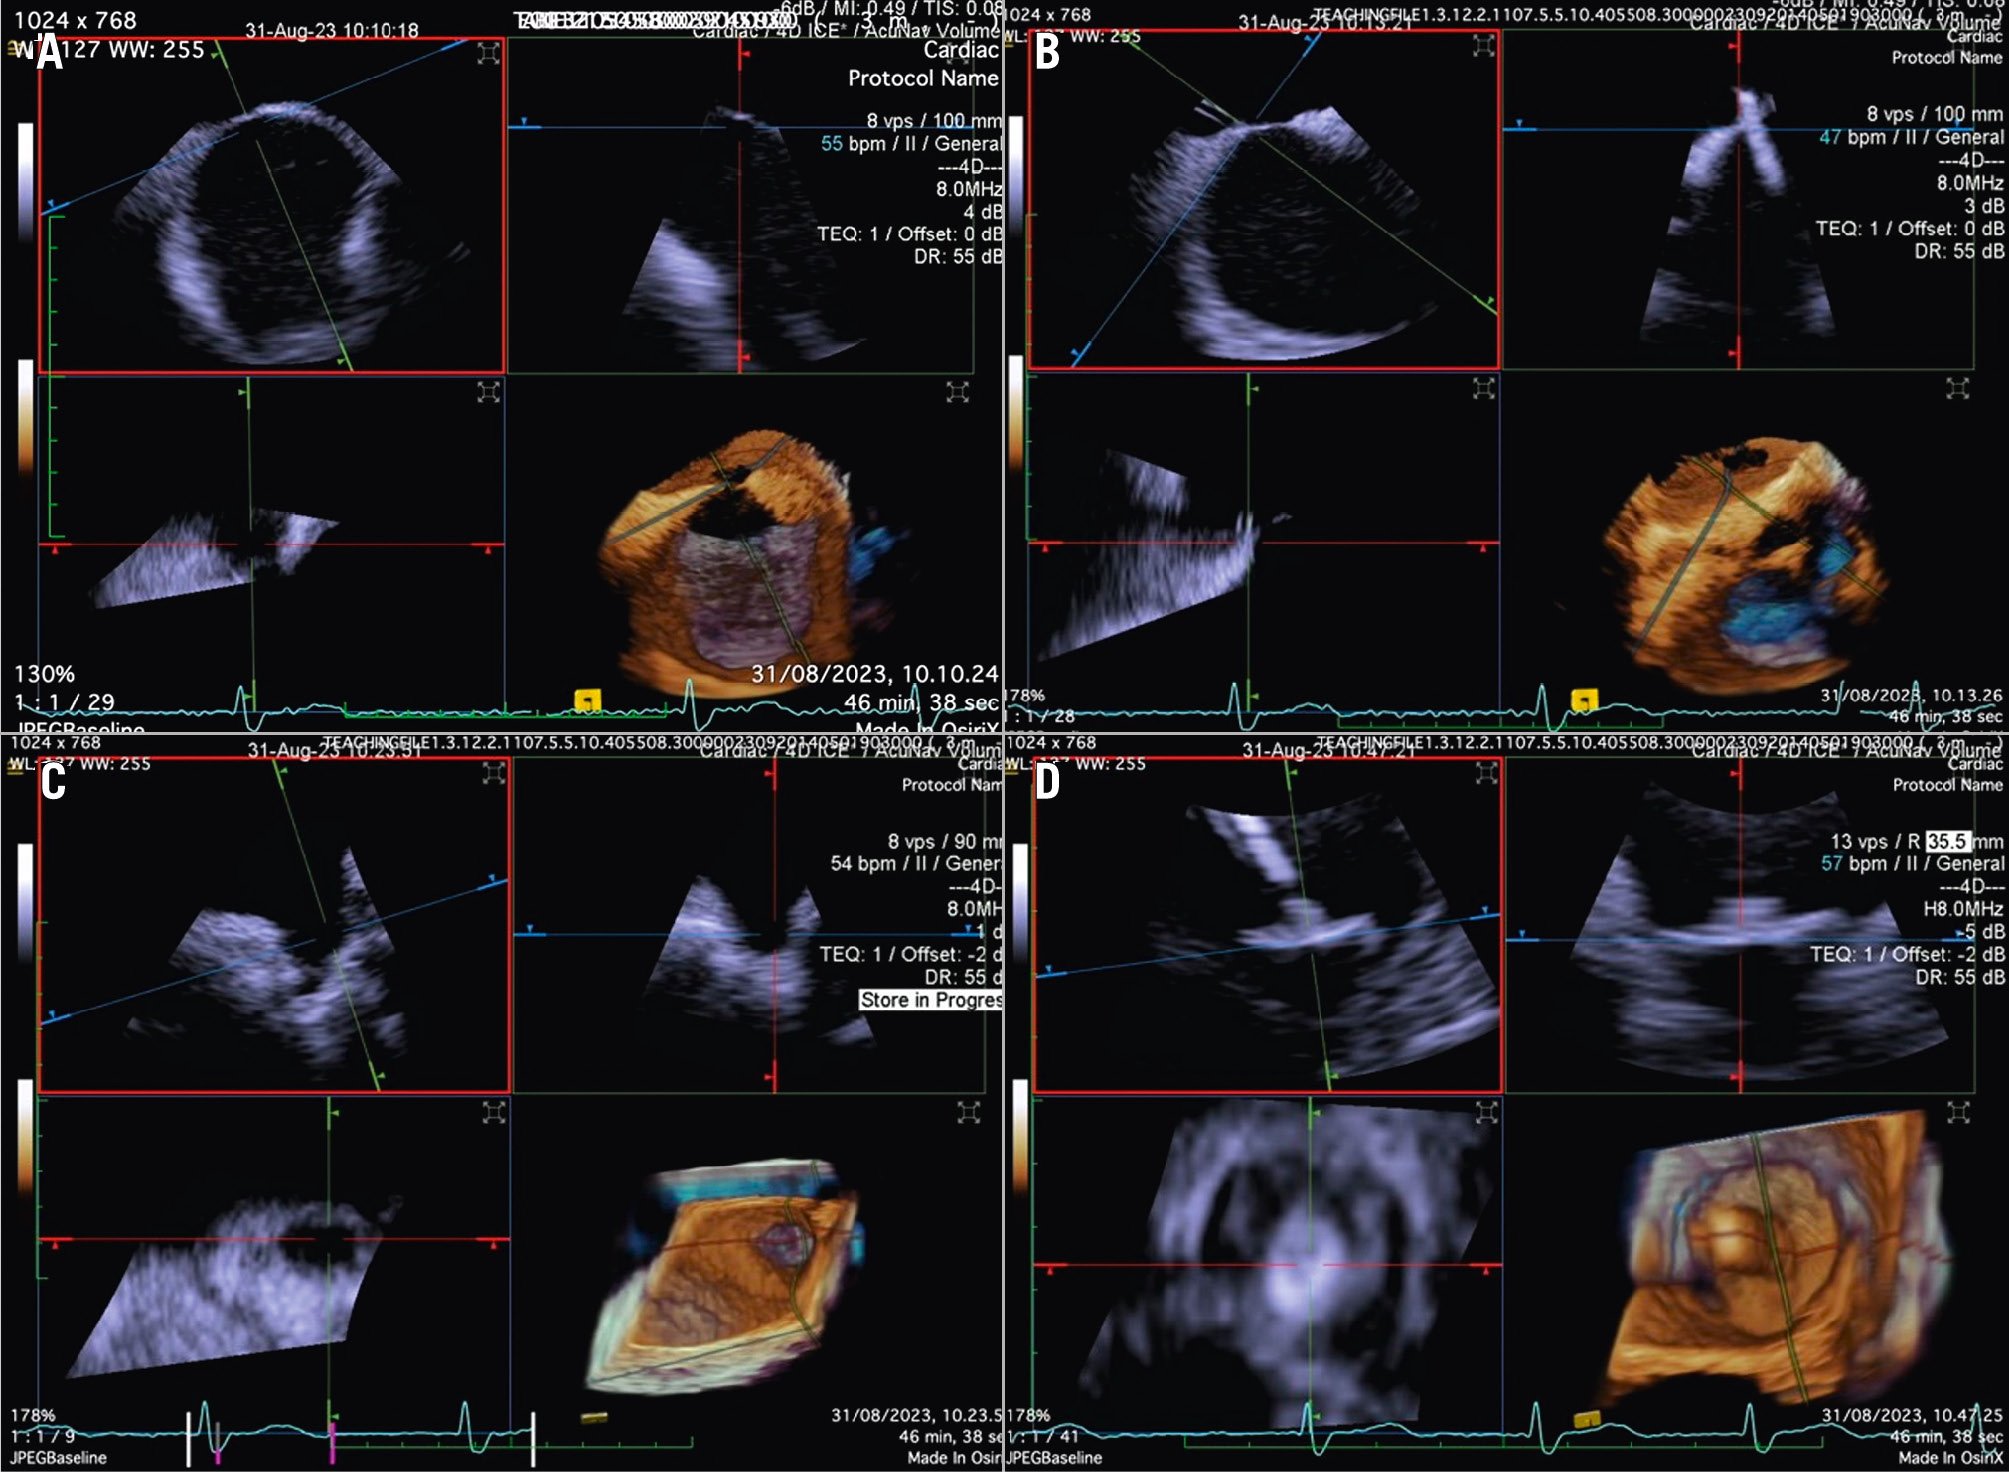

In the majority of LAAO procedures, inferior and posterior transseptal punctures are needed to obtain coaxial alignment between the delivery system and the LAA central axis. When using 3D ICE, the probe is initially best positioned in the middle of the left atrium with a frontal view of the LAA. In comparison to the use of 2D ICE, 3D ICE enables reliable measurements of the LAA dimensions at a chosen depth by using the MPR function (Figure 10). Once the measurements have been taken, the ICE catheter can be placed in the left upper pulmonary vein, with a good view of the LAA structures and the left circumflex artery. After the LAA occluder is deployed, ICE can be used to check its positioning, anchoring, size/device compression, and sealing. All of these items can be checked with 3D ICE using fewer positions than with 2D ICE (Figure 11, Moving image 14-Moving image 15-Moving image 16-Moving image 17).

Figure 11. Three-dimensional ICE-guided LAA occlusion. A) 3D MPR with probe in the right atrium to identify the best position of transseptal puncture. B) 3D MPR in real time to assess the catheter crossing the interatrial septum. C) 3D MPR to identify the shape and morphology of the LAA. D) 3D MPR in real time during deployment allows for precise positioning of the device and assessment of the position, anchor, size, and seal. 3D: three-dimensional; ICE: intracardiac echocardiography; LAA: left atrial appendage; MPR: multiplanar reconstruction